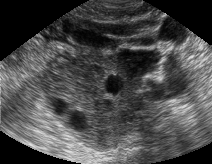

Contar y mesurar el número y tamaño de los folículos se realiza mediante exploración de la secuencia de planos en 2D de las imagenes captadas, lo cual es una tarea ardua y muy propensa a cometer errores. Esta reconstrucción puede verse en la imagen siguiente.

El actual trabajo detecta y cuenta estos folículos e forma automática. El mecanismo se basa en explorar toda la imagen buscando los bordes de los folículos, mas oscuros en la imagen que el fondo, y a partir de aqui , mesurar su tamaño y su forma. Este mecanismo es capaz de detectar foliculos de un tamaño entre 4 a 10 mm.

Mediante este mecanismo pueden detectarse con seguridad foliculos de entre 4 a 10 mm. Si bien la deteccion de foliculos mas pequeños esta sujeta a errores debido al ruido y es posible que se produzcan detecciones falsas.

Clinicamente, el interés se centra en folículos

entre 3 y 10 mm, por lo que la técnica debe ser depurada aun para

conseguir detecciones exitosas en folículos pequeños.